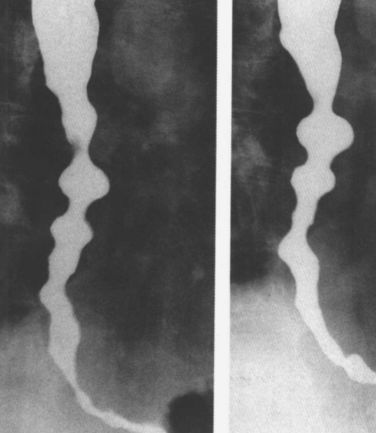

食管静脉曲张:蚯蚓样、串珠状。

食管重度静脉曲张

食管静脉曲张:食管黏膜呈现蚯蚓状